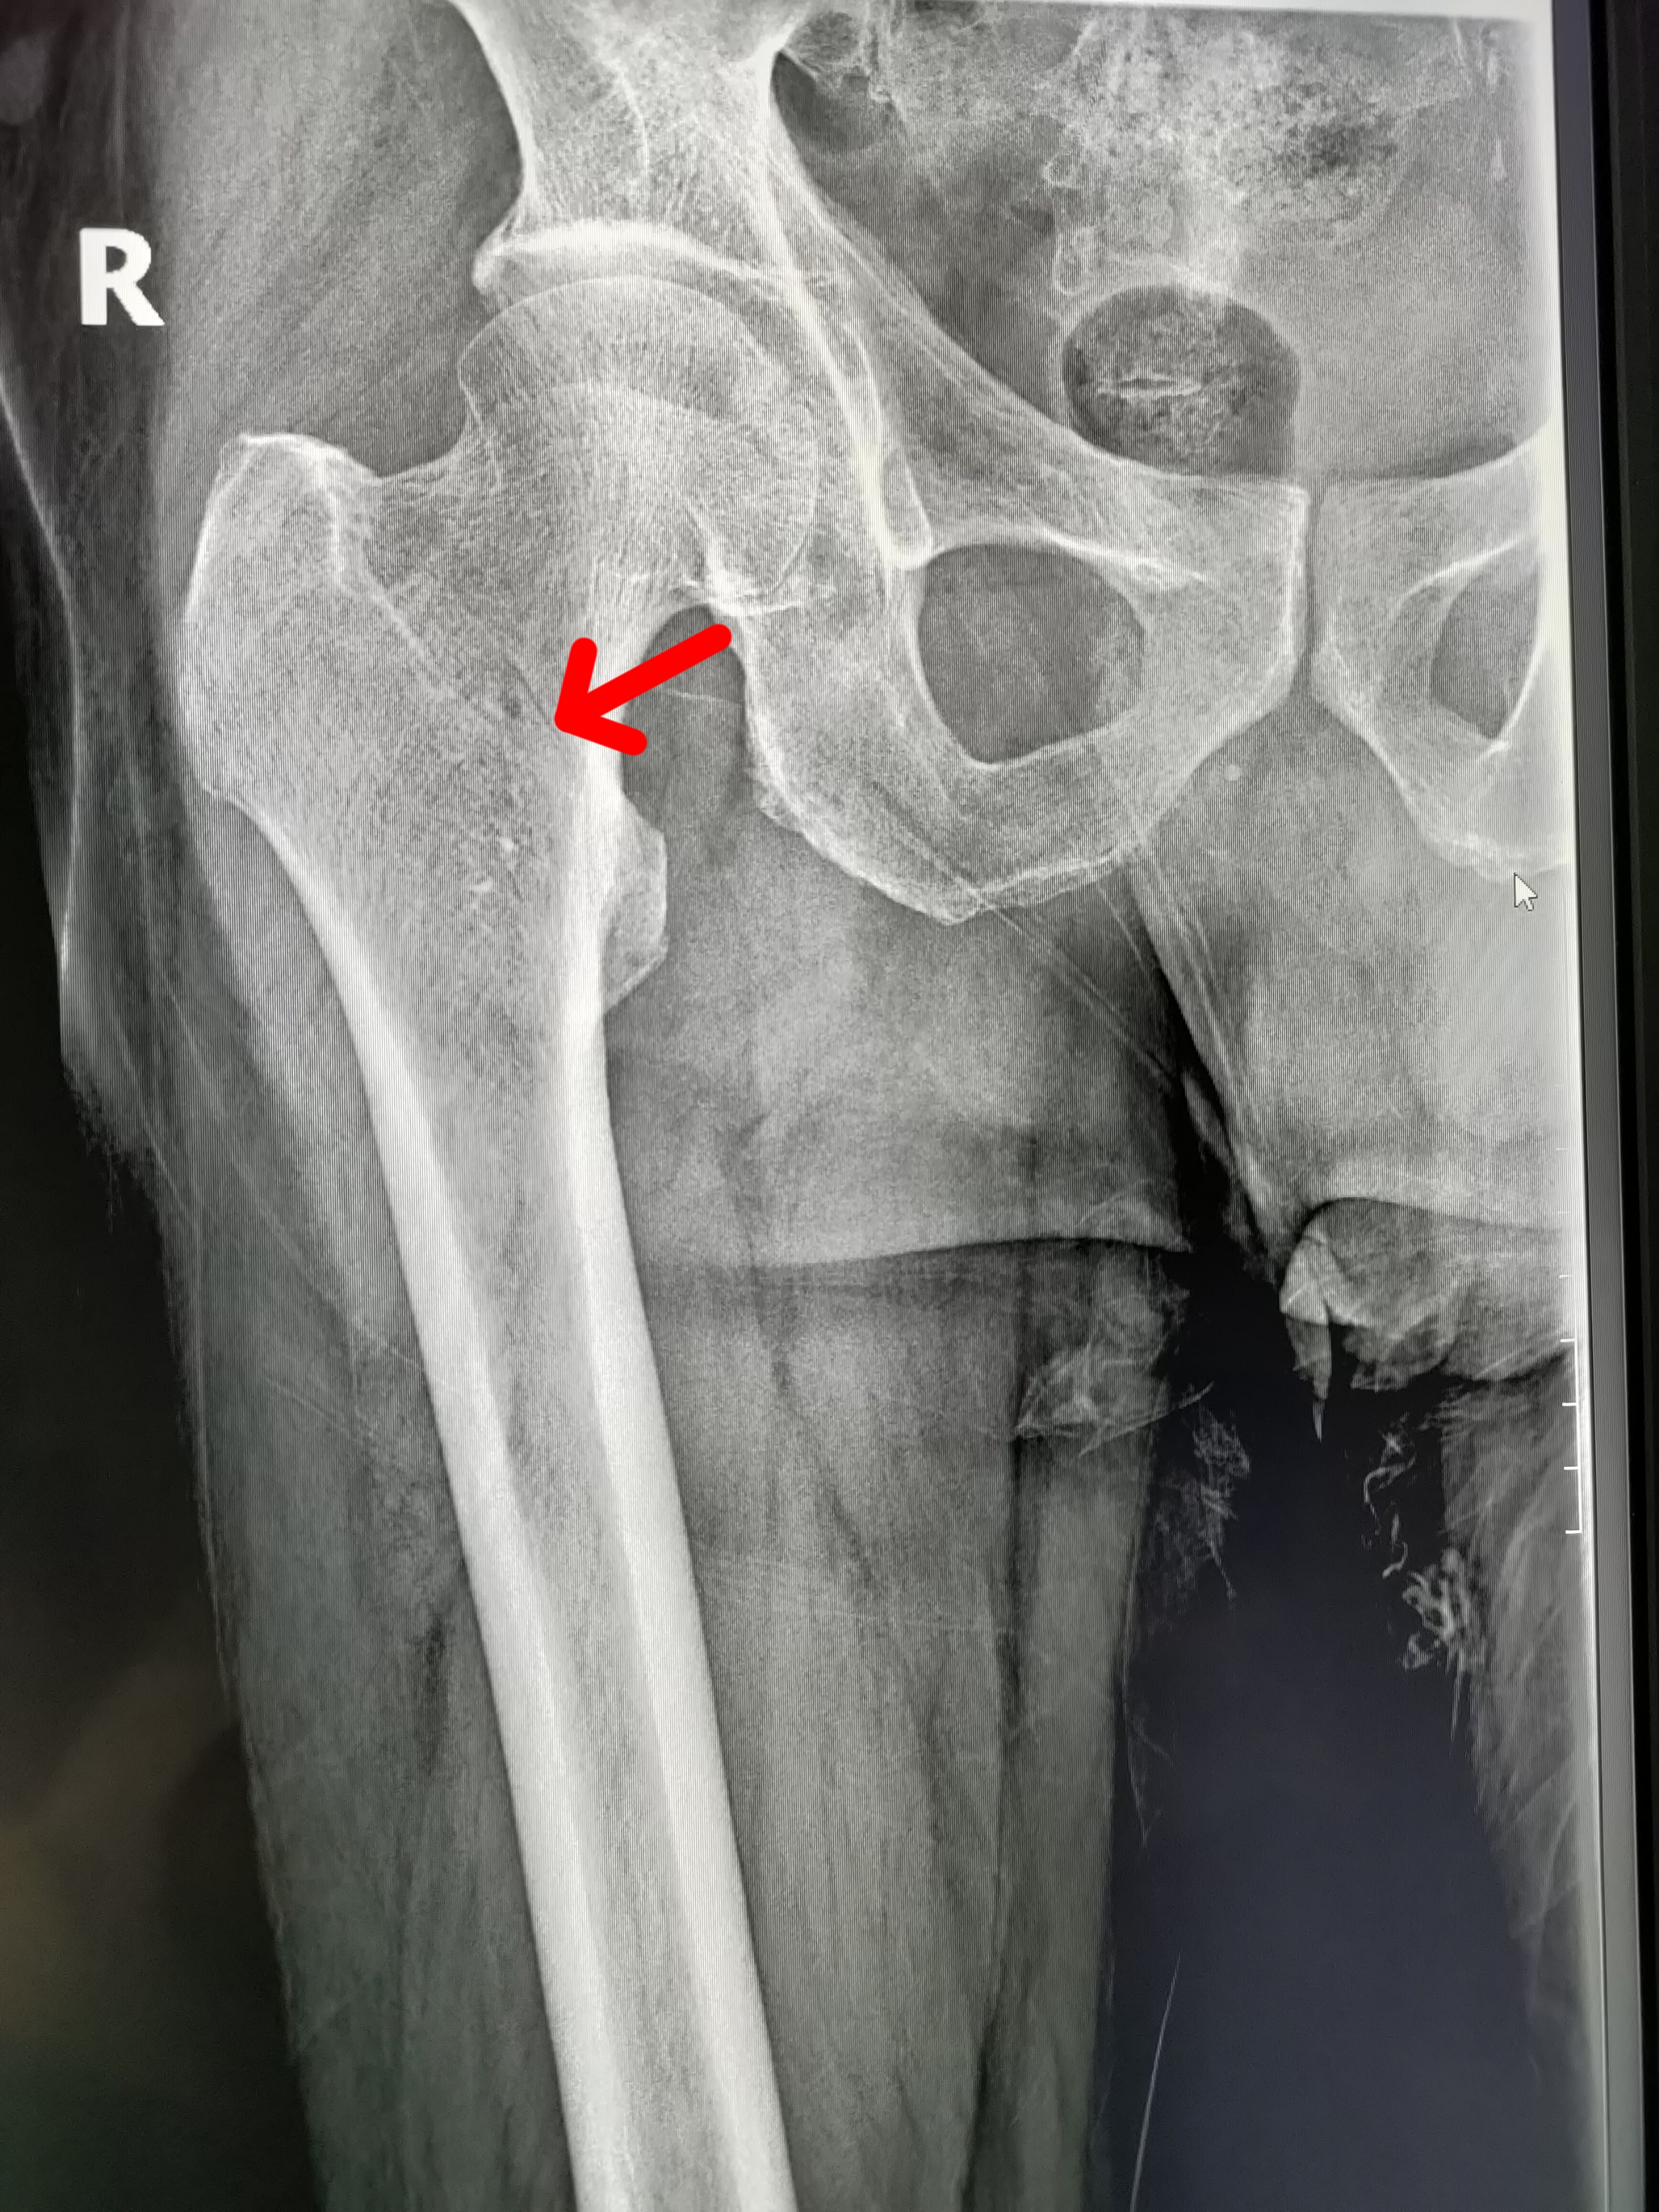

大清早的一外伤病人,男,67岁,因滑倒就诊,右股骨粗隆间骨折,就是我们

骨科科室play#右股骨粗隆间骨折evans 3型